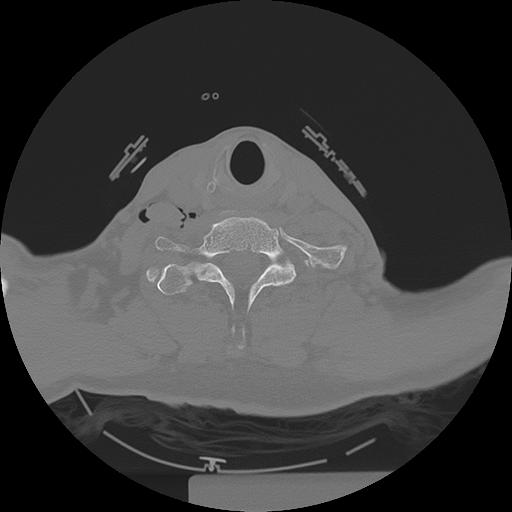

11 HUESO,,Axial,2.0,HUESO,,